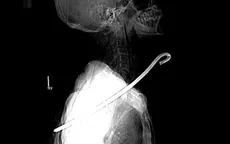

Cứu sống bệnh nhân bị cây sắt dài 30cm đâm thấu cổ VTV.vn - Bệnh viện Đa khoa tỉnh Hà Tĩnh vừa cứu sống một bệnh nhân bị cây sắt dài khoảng 30cm đâm thấu cổ, trung thất, phổi trái.